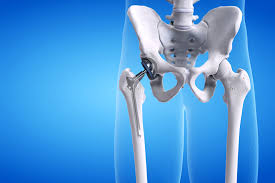

Precision hip replacement is an advanced orthopedic procedure designed to address complex hip joint conditions with a high degree of surgical accuracy. In Adilabad, this modern approach is gaining recognition because it combines medical expertise with technology-driven planning to improve joint alignment and function. Therefore, patients experiencing persistent hip discomfort or structural joint damage are increasingly exploring precision-based surgical options that focus on long-term joint stability and anatomical correctness rather than temporary symptom relief.

Precision hip replacement in Adilabad involves replacing the damaged components of the hip joint using meticulously planned surgical techniques. Moreover, this method prioritizes accurate implant positioning based on individual bone structure and joint orientation. As a result, the reconstructed joint is designed to closely replicate natural hip movement, which is essential for maintaining balance, posture, and overall musculoskeletal harmony in daily life.

Precision-based techniques enhance surgical accuracy by incorporating advanced imaging, digital planning, and alignment-focused instrumentation. Consequently, surgeons are able to visualize joint anatomy in greater detail before entering the operating environment. Moreover, this level of preparation allows for controlled execution during surgery, ensuring that implant placement supports optimal joint mechanics and minimizes alignment-related complications.